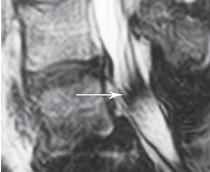

МРТ № 45

На МРТ № 45 наблюдается выраженный эпидурит.

Общее знание данного процесса необходимо для того, чтобы человек понимал, что может произойти с его организмом, если запустить заболевание и понадеяться, что всё пройдёт само собой. Если дело доходит до эпидурита, на это уже не махнёшь рукой, поскольку это, считайте, открытые ворота для всяких инфекций в «святая святых» организма — спинной и головной мозг. В конечном итоге это просто выбьет человека из колеи привычной жизни, сделает его неработоспособным, больным человеком, который уже экстренно будет нуждаться во врачебной помощи. Чтобы не доводить до таких последствий свой организм, давайте «посмотрим в корень» развития данного воспаления — эпидурита. Кстати, этот процесс чаще всего вызывают грыжи межпозвонковых дисков (особенно секвестрированные), реже — спондилёзы.